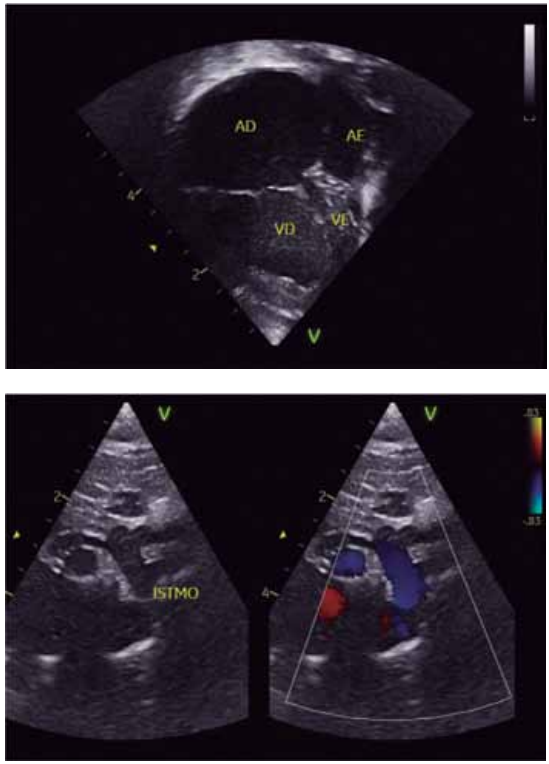

(Arquivo pessoal; imagens usadas com autorização)

Levando-se em consideração que o paciente apresenta concordância ventrículo-arterial, qual é o diagnóstico da cardiopatia congênita segundo as imagens apresentadas do ecocardiograma?